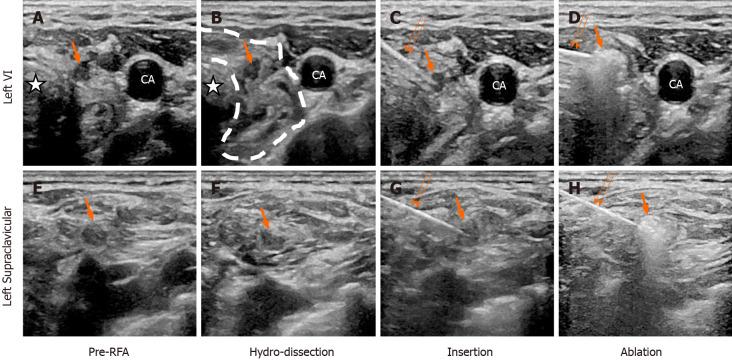

We report the case of a 56-year-old woman with cervical lymph node metastases of MTC. Four years previously, she had undergone a total thyroidectomy and neck lymph node dissection. A neck US revealed many enlarged nodes during the follow-up period. Moreover, the serum calcitonin jumped to 198.17 pg/mL, which strongly indicated the recurrence of MTC. Subsequently, two metastatic lymph nodes were confirmed by US-guided fine-needle aspiration-cytology and fine-needle aspiration-calcitonin, and then the patient was treated with RFA. Four months later, the neck US and a contrast-enhanced US showed obvious shrinkage in the ablation zones, and the serum calcitonin dropped to 11.80 pg/mL.

This case suggests that RFA may be an effective and safe treatment for local recurrent MTC.